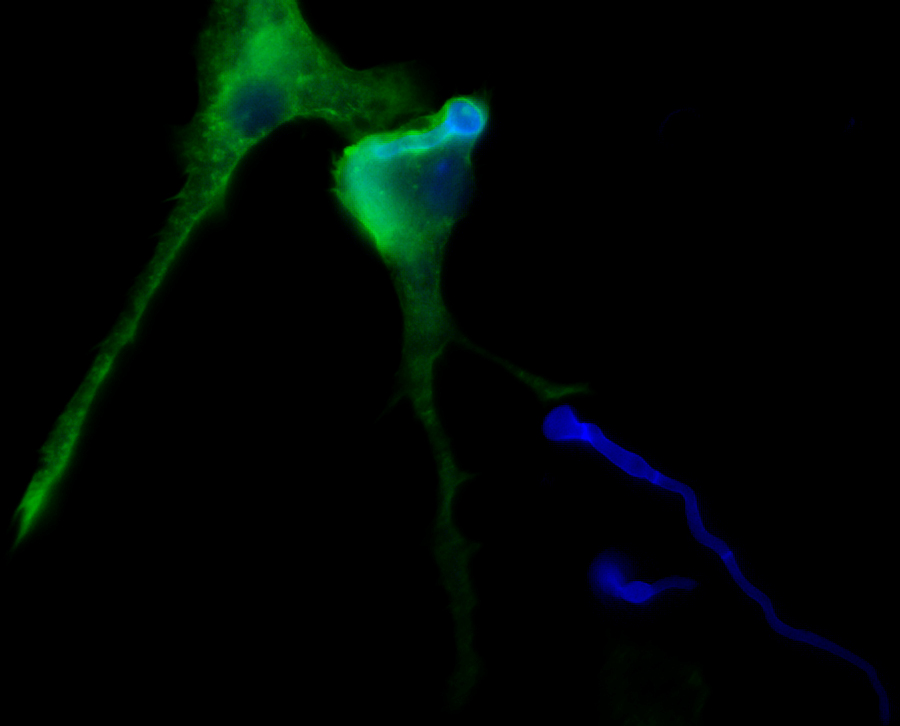

En este novedoso estudio, Microglial immune response is impaired against the neurotropic fungus Lomentospora prolificans, publicado en la revista Cellular Microbiology, los miembros del grupo de investigación de la UPV/EHU han descubierto que las células del sistema inmunitario del cerebro “responden pobremente” ante ese hongo.

“Los macrófagos son las células del sistema inmunitario encargadas de eliminar microorganismos y residuos de tejidos mediante su ingestión y eliminación. Estas células son residentes en cada tipo de tejido, pero en todos ellos tienen peculiaridades que los diferencian entre sí. Es decir, no son iguales los macrófagos del cerebro o microglía, que los del intestino, o los del pulmón. Creemos que estas diferencias son las que están detrás de la ineficiencia de la microglía y de que el hongo tenga facilidad de infectar el cerebro, causando un 100% de mortalidad en los pacientes que se infectan. Sin embargo, L. prolificans también debe tener algo especial en su biología que permita esto, ya que la comparación que hacemos en el artículo con otros microbios similares, nos muestra que este hongo es especialmente reacio a ser fagocitado”, explica Aize Pellón.

Fagocitosis de Lomentospora prolificans por la microglía. Tinción de florescencia en la que podemos observar el hongo (en azul; blanco de calcofluor) y las células de microglía con los filamentos de actina marcados (en verde; Faloidina-Atto 488). Se muestra alguna célula del hongo en el interior celular de la microglía, mientras que otras no han sido ingeridas.